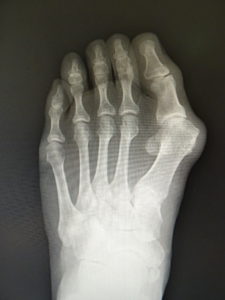

(図5)

手術前 手術後4年

(図6)

手術前 手術後

(図7)

真田理事長による手術の様子。外反母趾|症例 (左から 手術前、手術後、ワイヤ抜去後)